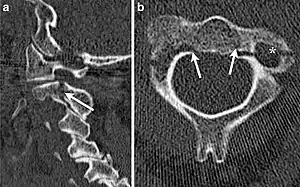

Hangman's fracture is the name given to a fracture of both pedicles (partes interarticulares) of the axis vertebra (C2) in the neck, and associated with a defect in the space between C2 and C3.[1]

It occurs as a result of a combination of hyperextension, flexion and compression in the neck.[1] There are generally three types.[1] Types I and II are typically managed with a hard collar, whereas surgically fusing C2 and C3 is required for type III.[1]

Although a hangman's fracture is unstable, survival from this fracture is relatively common, as the fracture itself tends to expand the spinal canal at the C2 level. It is not unusual for patients to walk in for treatment and have such a fracture discovered on X-rays. Only if the force of the injury is severe enough that the vertebral body of C2 is severely subluxed from C3 does the spinal cord become crushed, usually between the vertebral body of C3 and the posterior elements of C1 and C2.